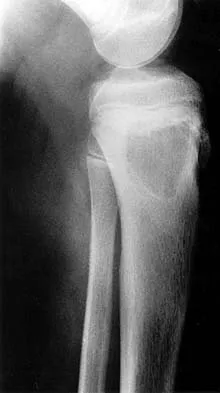

A 16-year-old boy has had thigh pain for the past several months. He denies any history of trauma. Examination reveals a large, deeply fixed, soft-tissue mass in the thigh. Laboratory results show an elevated erythrocyte sedimentation rate (ESR) and leukocytosis. A plain radiograph and MRI scan are shown in Figures 1a and 1b. Biopsy specimens are shown in Figures 1c and 1d. What is the most likely diagnosis?